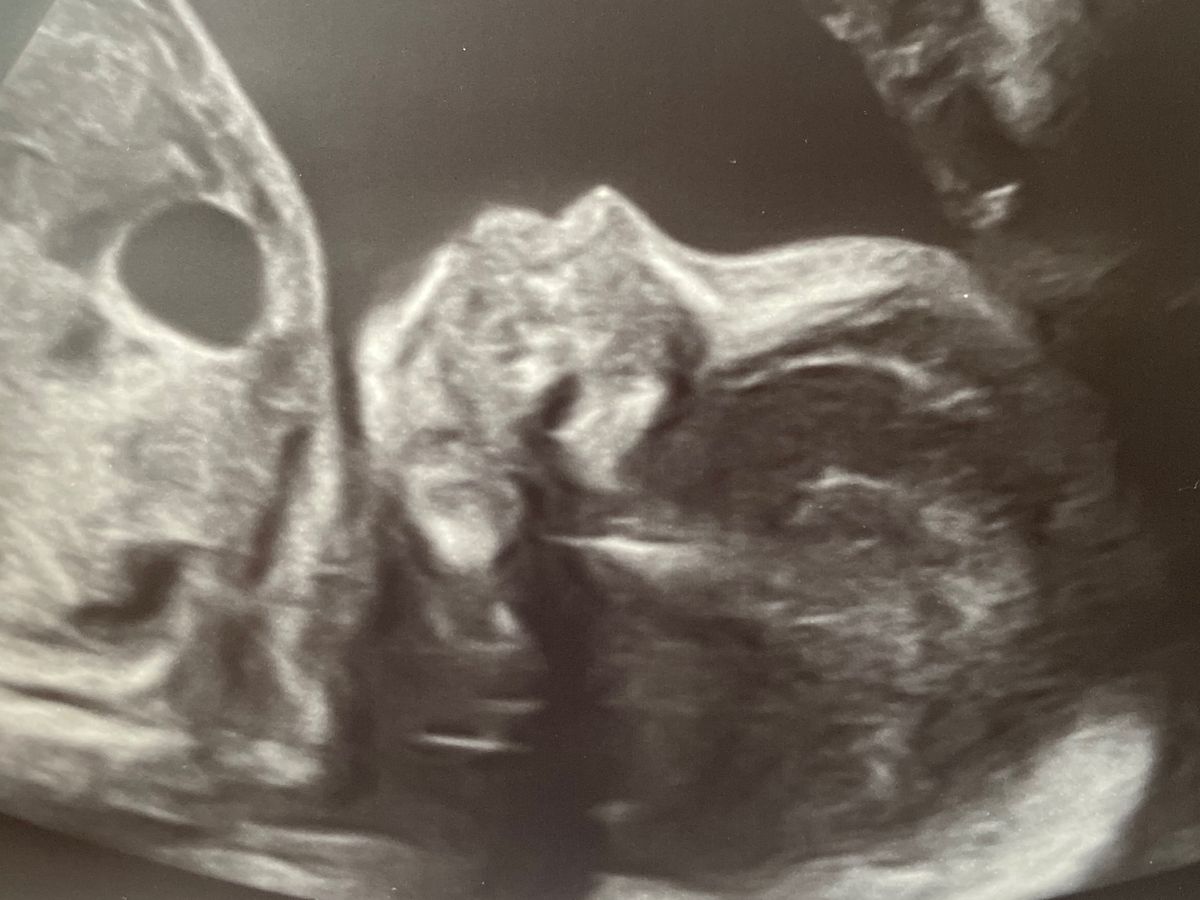

My name is Tara, and I’m very excited to become an aunt! My sister Cayla is 22 weeks pregnant with a precious little boy named Leo. We were saddened to hear that on his 20 week routine anatomy scan, he was found to have a Congenital Pulmonary Airway Malformation (CPAM). In simple terms, Leo has a mass in his lung. Although it is considered benign, it is significant enough to be pushing on his heart. Cayla, and her husband, Joe, live in a remote area and have been advised by her physicians to seek treatment at Childrens Hospital of Cincinnati. This hospital has a highly acclaimed team of doctors that are trained to care for kiddos with Leo’s rare situation. Unfortunately, the ultrasounds have shown that the mass has continued to grow. The doctors are recommending that Cayla have in depth ultrasounds twice a week in Cincinnati. This is a 400 mile round trip for them each visit. That being said, I’m asking for help. Whether it be financially for gas, food, medical bills or prayers. Any help will be greatly appreciated.